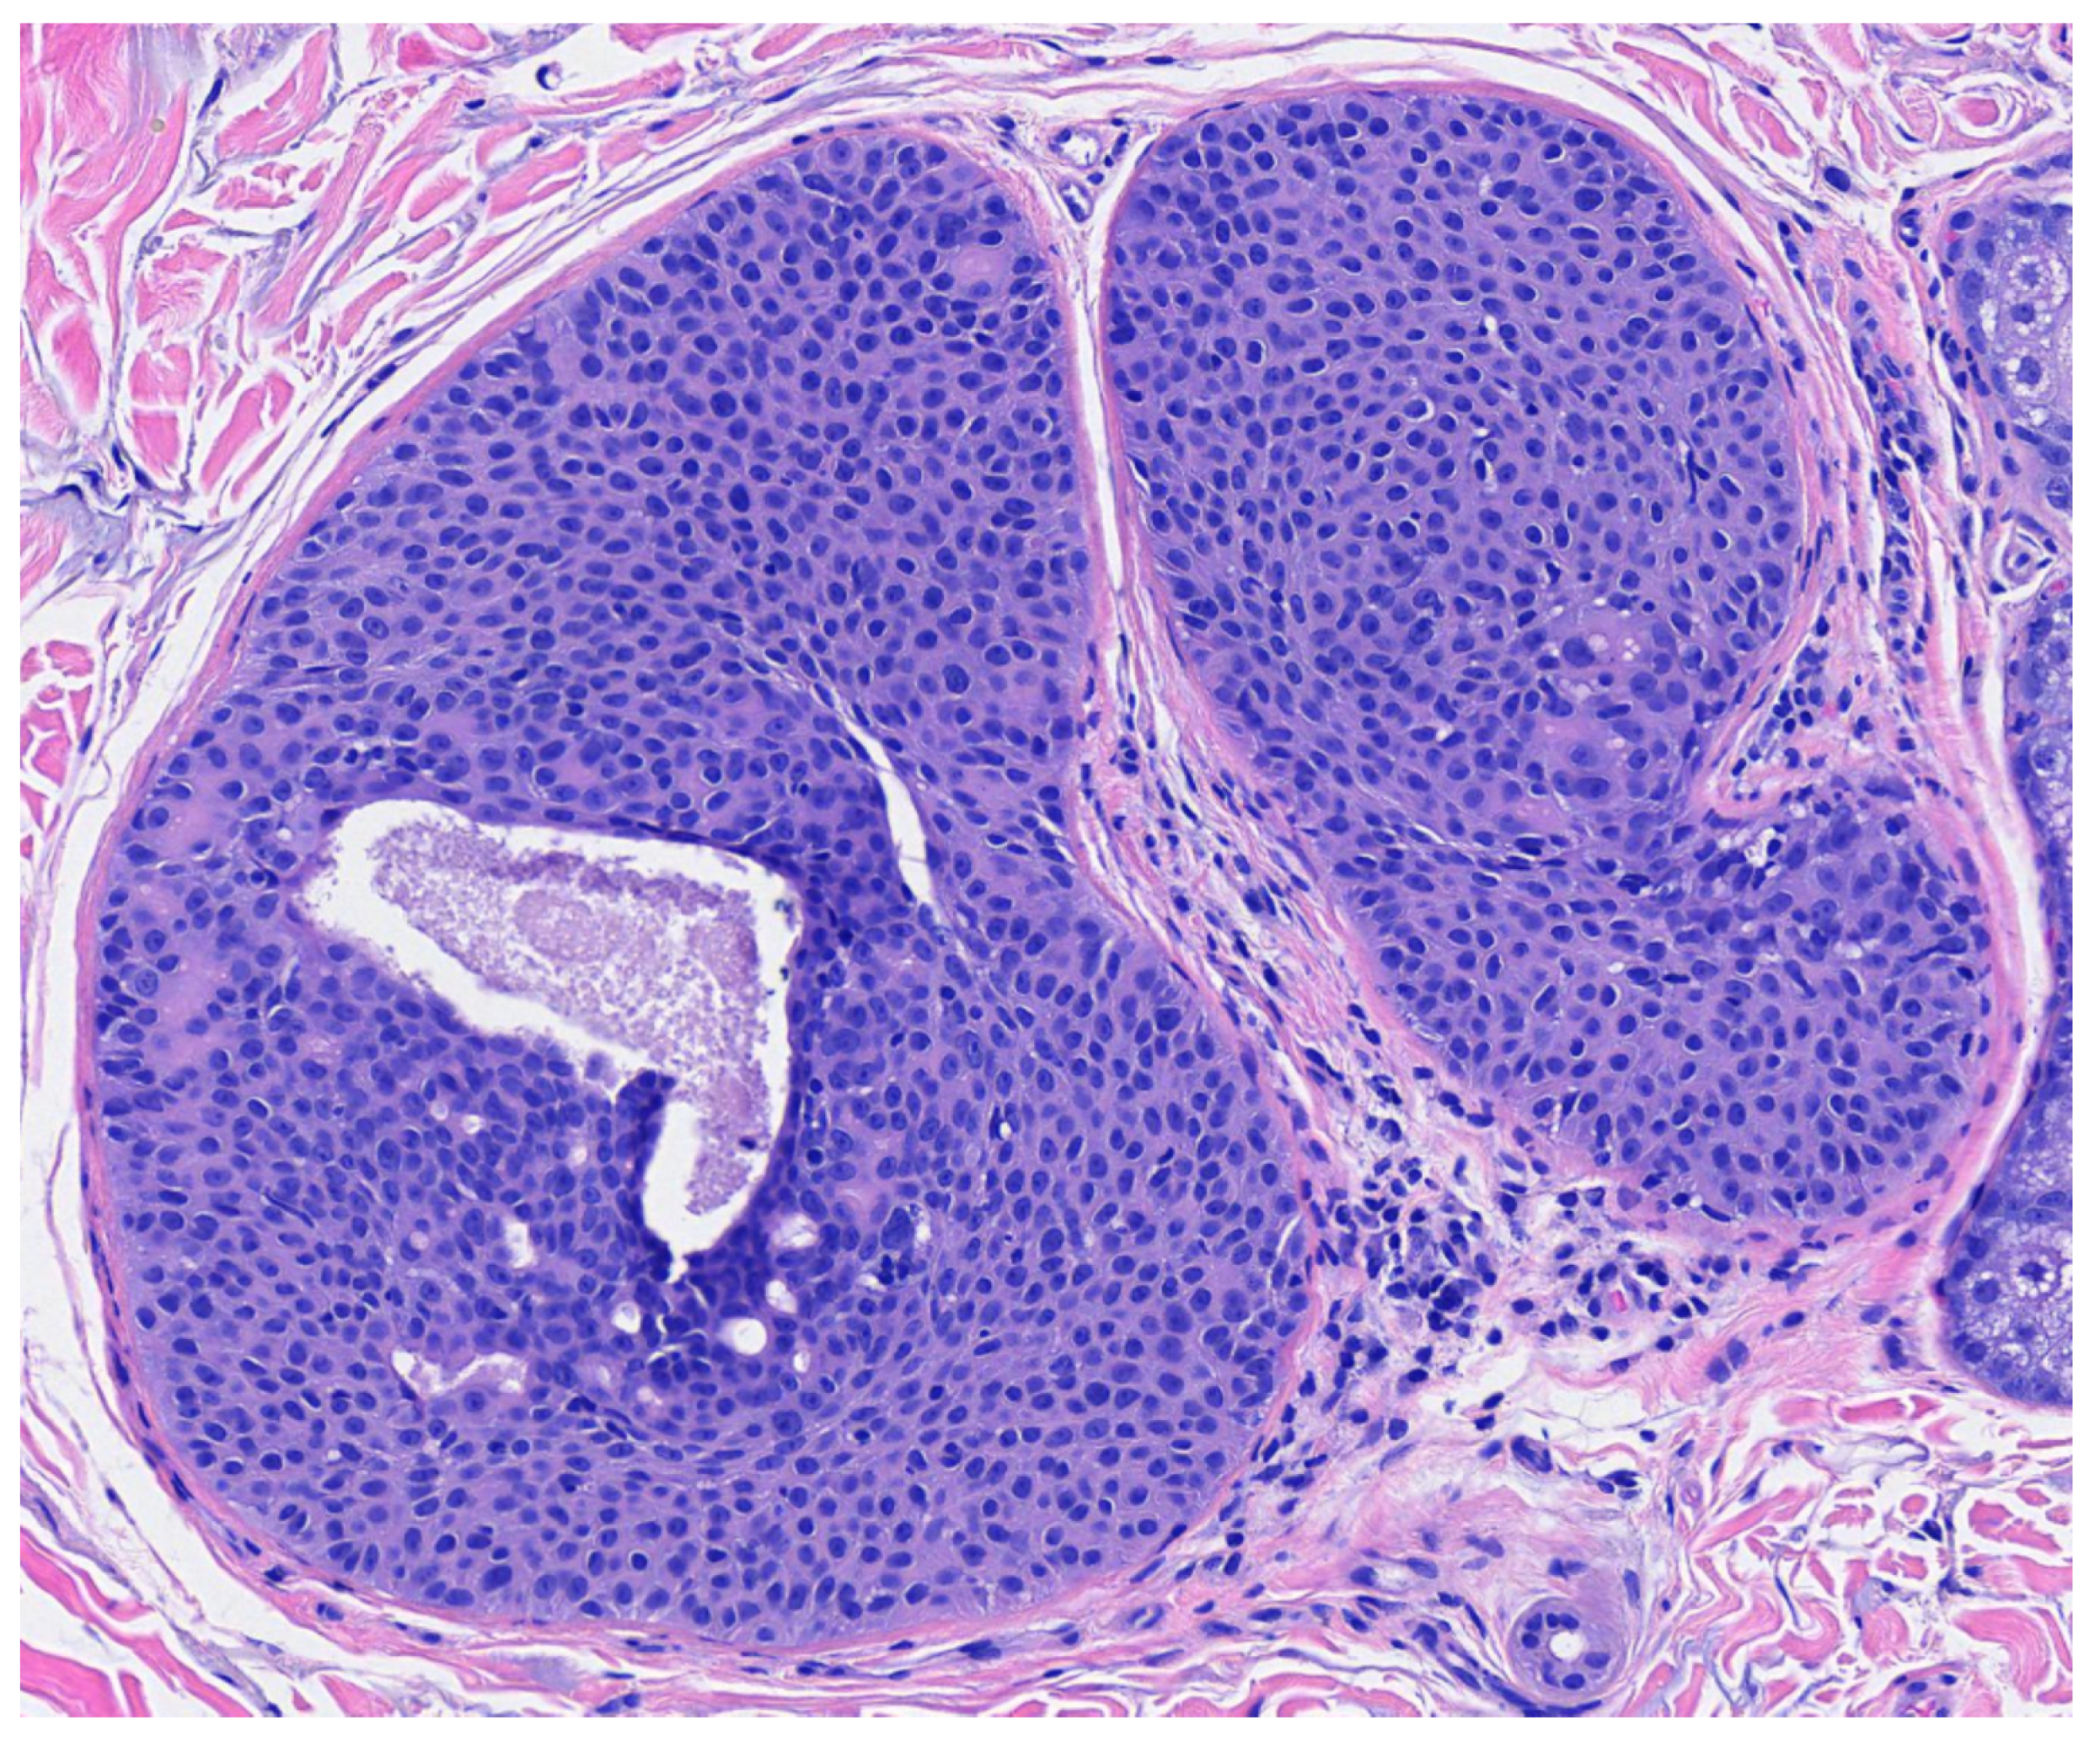

Figure 4. Higher magnification reveals small poriod cells with round to oval nuclei and scant cytoplasm. Ductal lumen formation is present (H & E, 10×).

Poroma variants are differentiated based on the predominant cell type present and the degree of epidermal/dermal involvement [2]. However, multiple variants can exist within the same lesion. DDTs are primarily confined to the superficial dermis and are composed of small solid and cystic nodular aggregates of poroid, cuticular, and clear cells (Figure 3, Figure 4 and Figure 5) [2]. Eccrine poromas are also composed of all three cell types, but are primarily located in the epidermis and superficial dermis. Hidroacanthoma simplex is mainly composed of poroid cells, less cuticular cells, and no clear cells [2]. It is confined to the epidermis. Poroid hidradenoma contains a mixture of all three cell types and is also confined to the dermis [2]. In contrast to DDT, poroid hidradenomas have large aggregates of solid and cystic components and extend deeper into the reticular dermis and even subcutis [2].